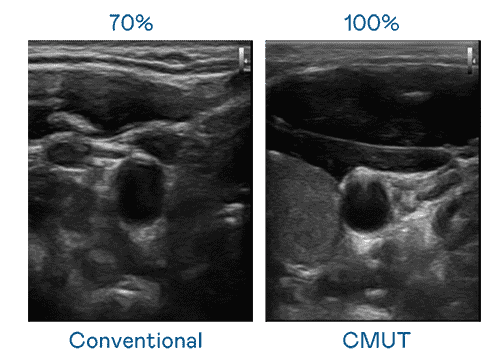

CMUT 技术是一种用电容式微机电元件来产生超音波讯号的技术。。与传统 PZT 压电式技术相比,,CMUT 频宽增加 30%,,更宽频的超音波讯号让影像解析度大幅提升,,,,是实现高影像品质医疗超音波扫描、、、、促进精准医疗发展的关键技术。。

大频宽带来超清晰影像

超音波影像的解析度高低,,,首先取决于探头能发出的讯号频宽。。z6mg·人生就是博 CMUT 可提供高清晰的超音波讯号,,,提供高频宽、、、、高灵敏度、、、、影像纹理细节更高的超音波影像,,,,协助医护人员缩短影像判读时间及利用精准的医疗影像进行诊断。。。。